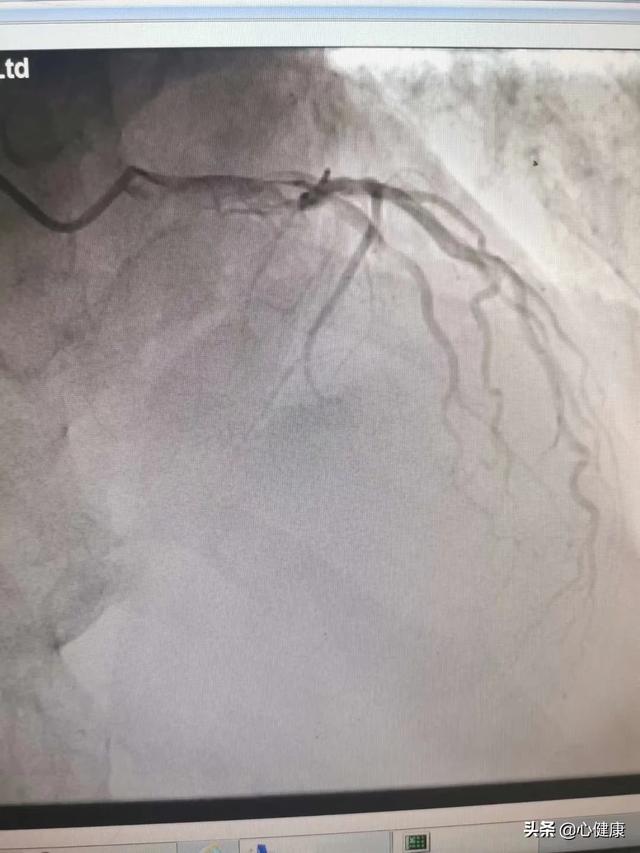

Un cardiogramme, ou plus précisément une coronarographie, est un examen qui permet de déterminer la présence de plaques d'athérome sur les parois des vaisseaux sanguins (artères coronaires) qui alimentent le cœur en sang. Si c'est le cas, quel est le degré de rétrécissement de la lumière des vaisseaux sanguins, afin de déterminer s'il y a une maladie des artères coronaires, ce qui est l'étalon-or pour le diagnostic de la maladie des artères coronaires.

Une aiguille à demeure est placée dans le bras et, lors d'un examen par tomodensitométrie, un agent de contraste est rapidement injecté, qui s'écoulera dans les vaisseaux sanguins du cœur, puis une tomodensitométrie est réalisée et, enfin, une imagerie tridimensionnelle des artères coronaires est effectuée en arrière-plan pour voir s'il y a une sténose des vaisseaux sanguins coronaires et pour juger du degré de sténose. Cependant, cette technique n'est pas aussi précise que la coronarographie en raison de facteurs tels que la coopération, le rythme cardiaque, la respiration, etc. Afin de prévenir la néphropathie de contraste, vous devez boire beaucoup d'eau après l'examen afin d'excréter le produit de contraste le plus rapidement possible. Les personnes dont la fonction rénale est anormale doivent être évaluées par un médecin avant de décider si elles peuvent subir cet examen.

Le changement pathologique de la maladie coronarienne est le rétrécissement de l'artère coronaire dû à la formation d'une plaque d'athérome dans l'artère coronaire. En général, une sténose de l'artère coronaire de plus de 50 % peut être diagnostiquée comme une maladie coronarienne. Le diagnostic de sténose de l'artère coronaire peut être établi par le scanner coronaire et la coronarographie, et l'électrocardiographie peut être utilisée comme test auxiliaire pour l'ischémie myocardique. Parmi ces examens, la coronarographie, qui est l'"étalon-or" du diagnostic des maladies coronariennes, est plus précise. Cependant, comme la coronarographie est un examen invasif qui comporte certains risques et qui est coûteux, de nombreux patients la rejettent.